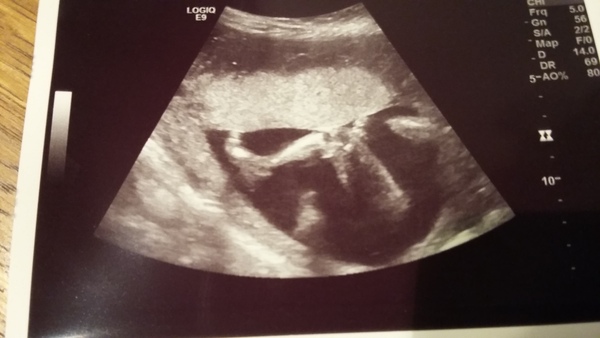

NFMS: It's all good! (Phew!) Grin

Flashing a bit of leg...

Yay! Congrats for happy scan 5hell!

Wow 5hell that's an amazing picture!

wicked scan 5hell! did you find out the flavour?

Thanks guys, we were lucky to get some lovely pics!

Yes we found out the flavour, not telling IRL, but happy to tell u guys it's a boy-by!

I was all 'too cool for school' until she said it's a boy. ..made it more real and I shed a little tear Smile

That's a fab scan photo 5hell! Glad all OK and hurray for a boybe!

Awww 5hell lovely news - and what a lovely little chunky leg!

Aw 5hell that pic is so cute! That's a proper leg there!!

Hooray for a lovely boybee 5hell!